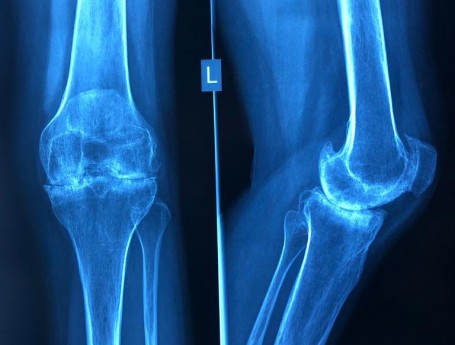

Total Knee Replacement